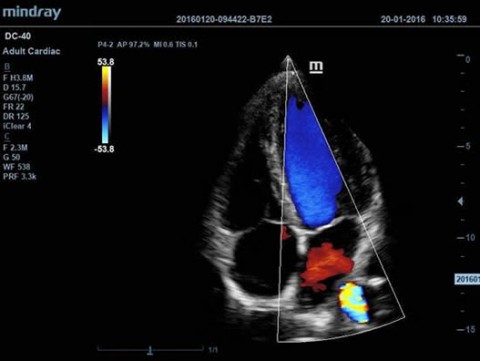

Аппарат ультразвуковой диагностический DC-40

Аппарат ультразвуковой диагностический DC-40 - 393 400 руб.

- Режимы сканирования B/M/Цветовой доплер CDI/Цветной M/Энергетический доплер PD/Направленный энергетический доплер Dir.PD

- CW Module - Блок постоянно-волнового доплера CW

- ECG Module (ICE) - Модуль регистрации физиологических сигналов (ЭКГ) стандарта ICE

- TDI (Tissue Doppler Imaging, includes TVI, TEI, TVD and TVM) - Тканевой допплер, включая цветное картирование, импульсный тканевой допплер, энергетический тканевой допплер и тканевой М-режим

- Free Xros M™ (Anatomical M-mode) - Анатомический М-режим (до 3-х срезов)

- Free Xros CM™ (Curved Anatomical M-Mode, TDI should be configured at the same time ) - Огибающий анатомический М-режим (необходима установленная опция TDI)

Применение УЗИ:

Общая диагностика, Кардиология